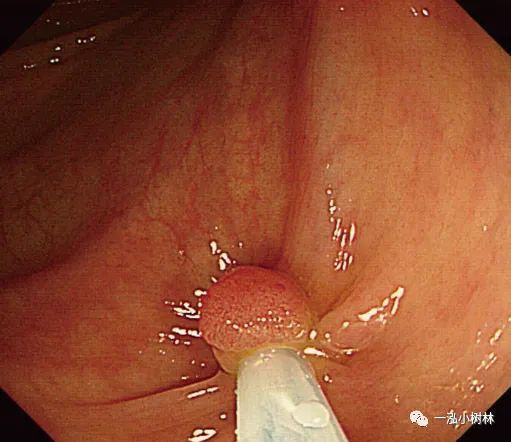

图5d 对病变进行机械性横切

图5e 对病变进行机械性横切

图5f 息肉取出后出血

图5g 黏膜出血止血

图5h 可见息肉边缘正常黏膜的标本